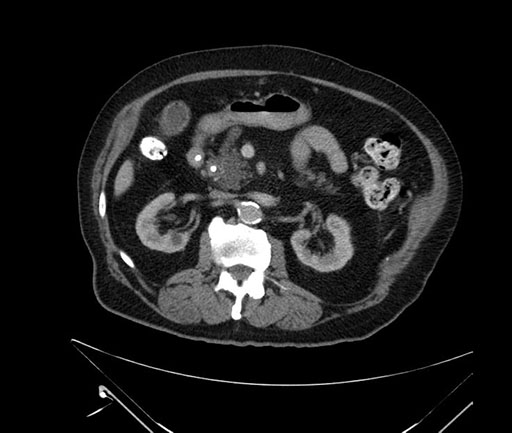

Whipple (pancreaticoduodenectomy) [case 7]

Coronal - stented